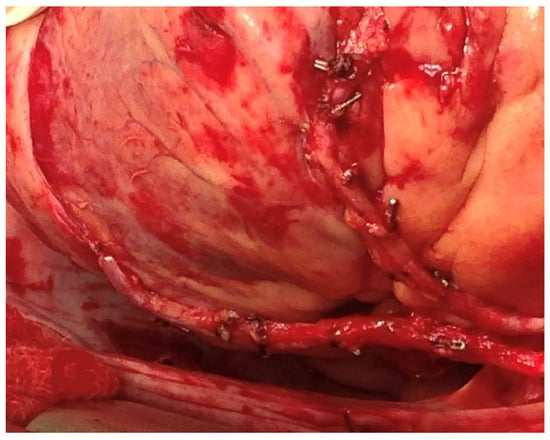

2.4. The Impact of the Anastomotic Technique